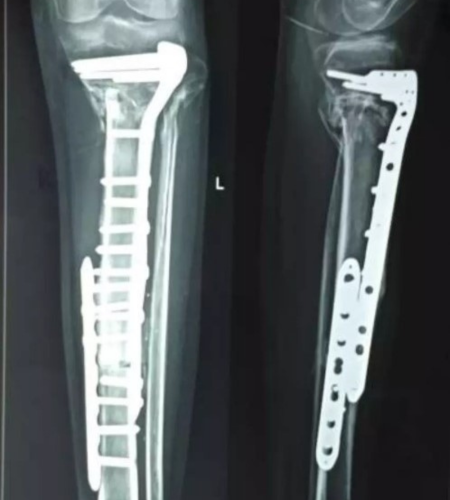

Once the bone is adequately sterilized, it is thawed, prepared, and re-implanted into the patient for biological reconstruction. The treated bone can then be fixed using plates, screws, or intramedullary devices.